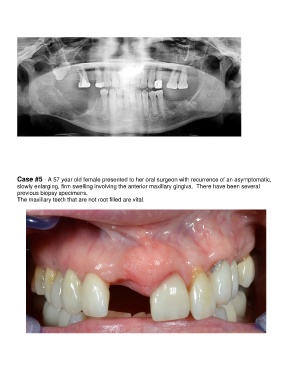

Case #5 - A 57 year old female presented to her oral surgeon with recurrence of an asymptomatic,

slowly enlarging, firm swelling involving the anterior maxillary gingiva.  There have been several

previous biopsy specimens.

The maxillary teeth that are not root filled are vital.